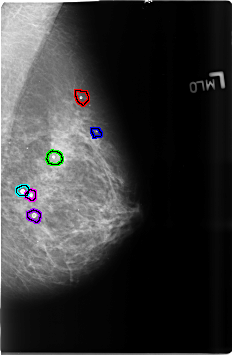

B_3684_1.RIGHT_MLO

FILE: B_3684_1.RIGHT_MLO.OVERLAY

TOTAL_ABNORMALITIES 7

ABNORMALITY 1

LESION_TYPE CALCIFICATION TYPE ROUND_AND_REGULAR-EGGSHELL DISTRIBUTION N/A

ASSESSMENT 2

SUBTLETY 3

PATHOLOGY BENIGN_WITHOUT_CALLBACK

TOTAL_OUTLINES 1

BOUNDARY

ABNORMALITY 2

ABNORMALITY 3

ABNORMALITY 4

ABNORMALITY 5

ABNORMALITY 6

TOTAL_OUTLINES 2

ABNORMALITY 7